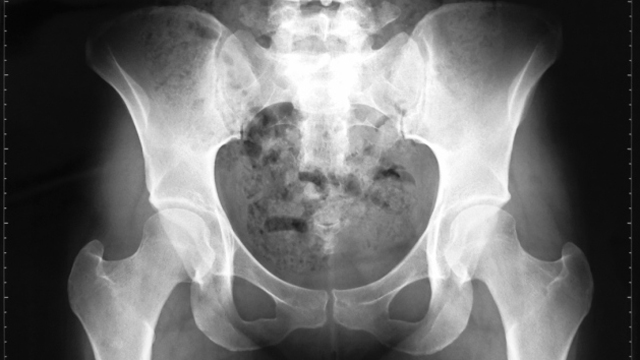

La dieta, el ejercicio y algunos hábitos muy sencillos pueden ayudar a tus huesos. Retrasa su envejecimiento para vivir mejor ¡Nosotros te enseñamos cómo!